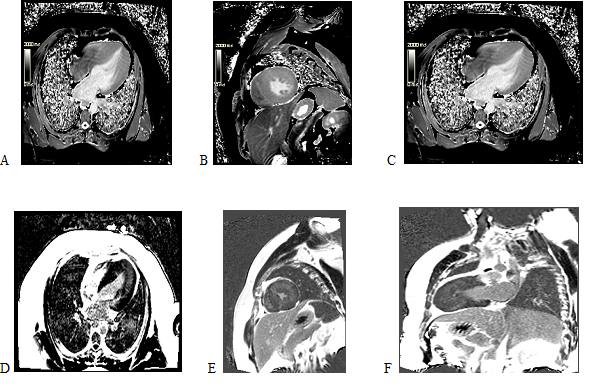

Xəstə 26 yaş, kişi

Bariatrik əməliyyat üçün kardioloq kons olunur.

Şikayətlət: bayılma(1 dəfə), təngnəfəslik, boğulma

EKQ: I,II,V1-V6 aparmalarda T dalğa neqayivliyi qeyd edilir.

EXO: LVEF-60%, LA-37 mm, LV 55/20 mm, mid-apikal hipertrofiya(mid septumda 24 mm, mid anterior 22 mm, apikal seqmentlər 23-24 mm qeyd edilir)- Yamaquçi sindromu?

HCM-SCD risk scoru:5.7% Xəstəyə Kardiak MRT və Holer-monitoring tövsiyə edildi. Holter-monitoringdə davamlı və davamsız aşkarlanmadı.

Kardiak-MR: Mid-apikal HKMP təsdiqləndi. Yamaquçi sindromu diaqnozu təsdiq edildi. T1 mappingdə bir neçə seqmentdə maping dəyərləri artmış, lakin diffuz fibroz görülmədi. Həlledici məqam xəstədə midmiokardial LGE 15% olaraq hesablandı. Bu risk dəyərləndirməsini xəstə üçün dəyişdi və İCD implantasiyası qərarı verildi.